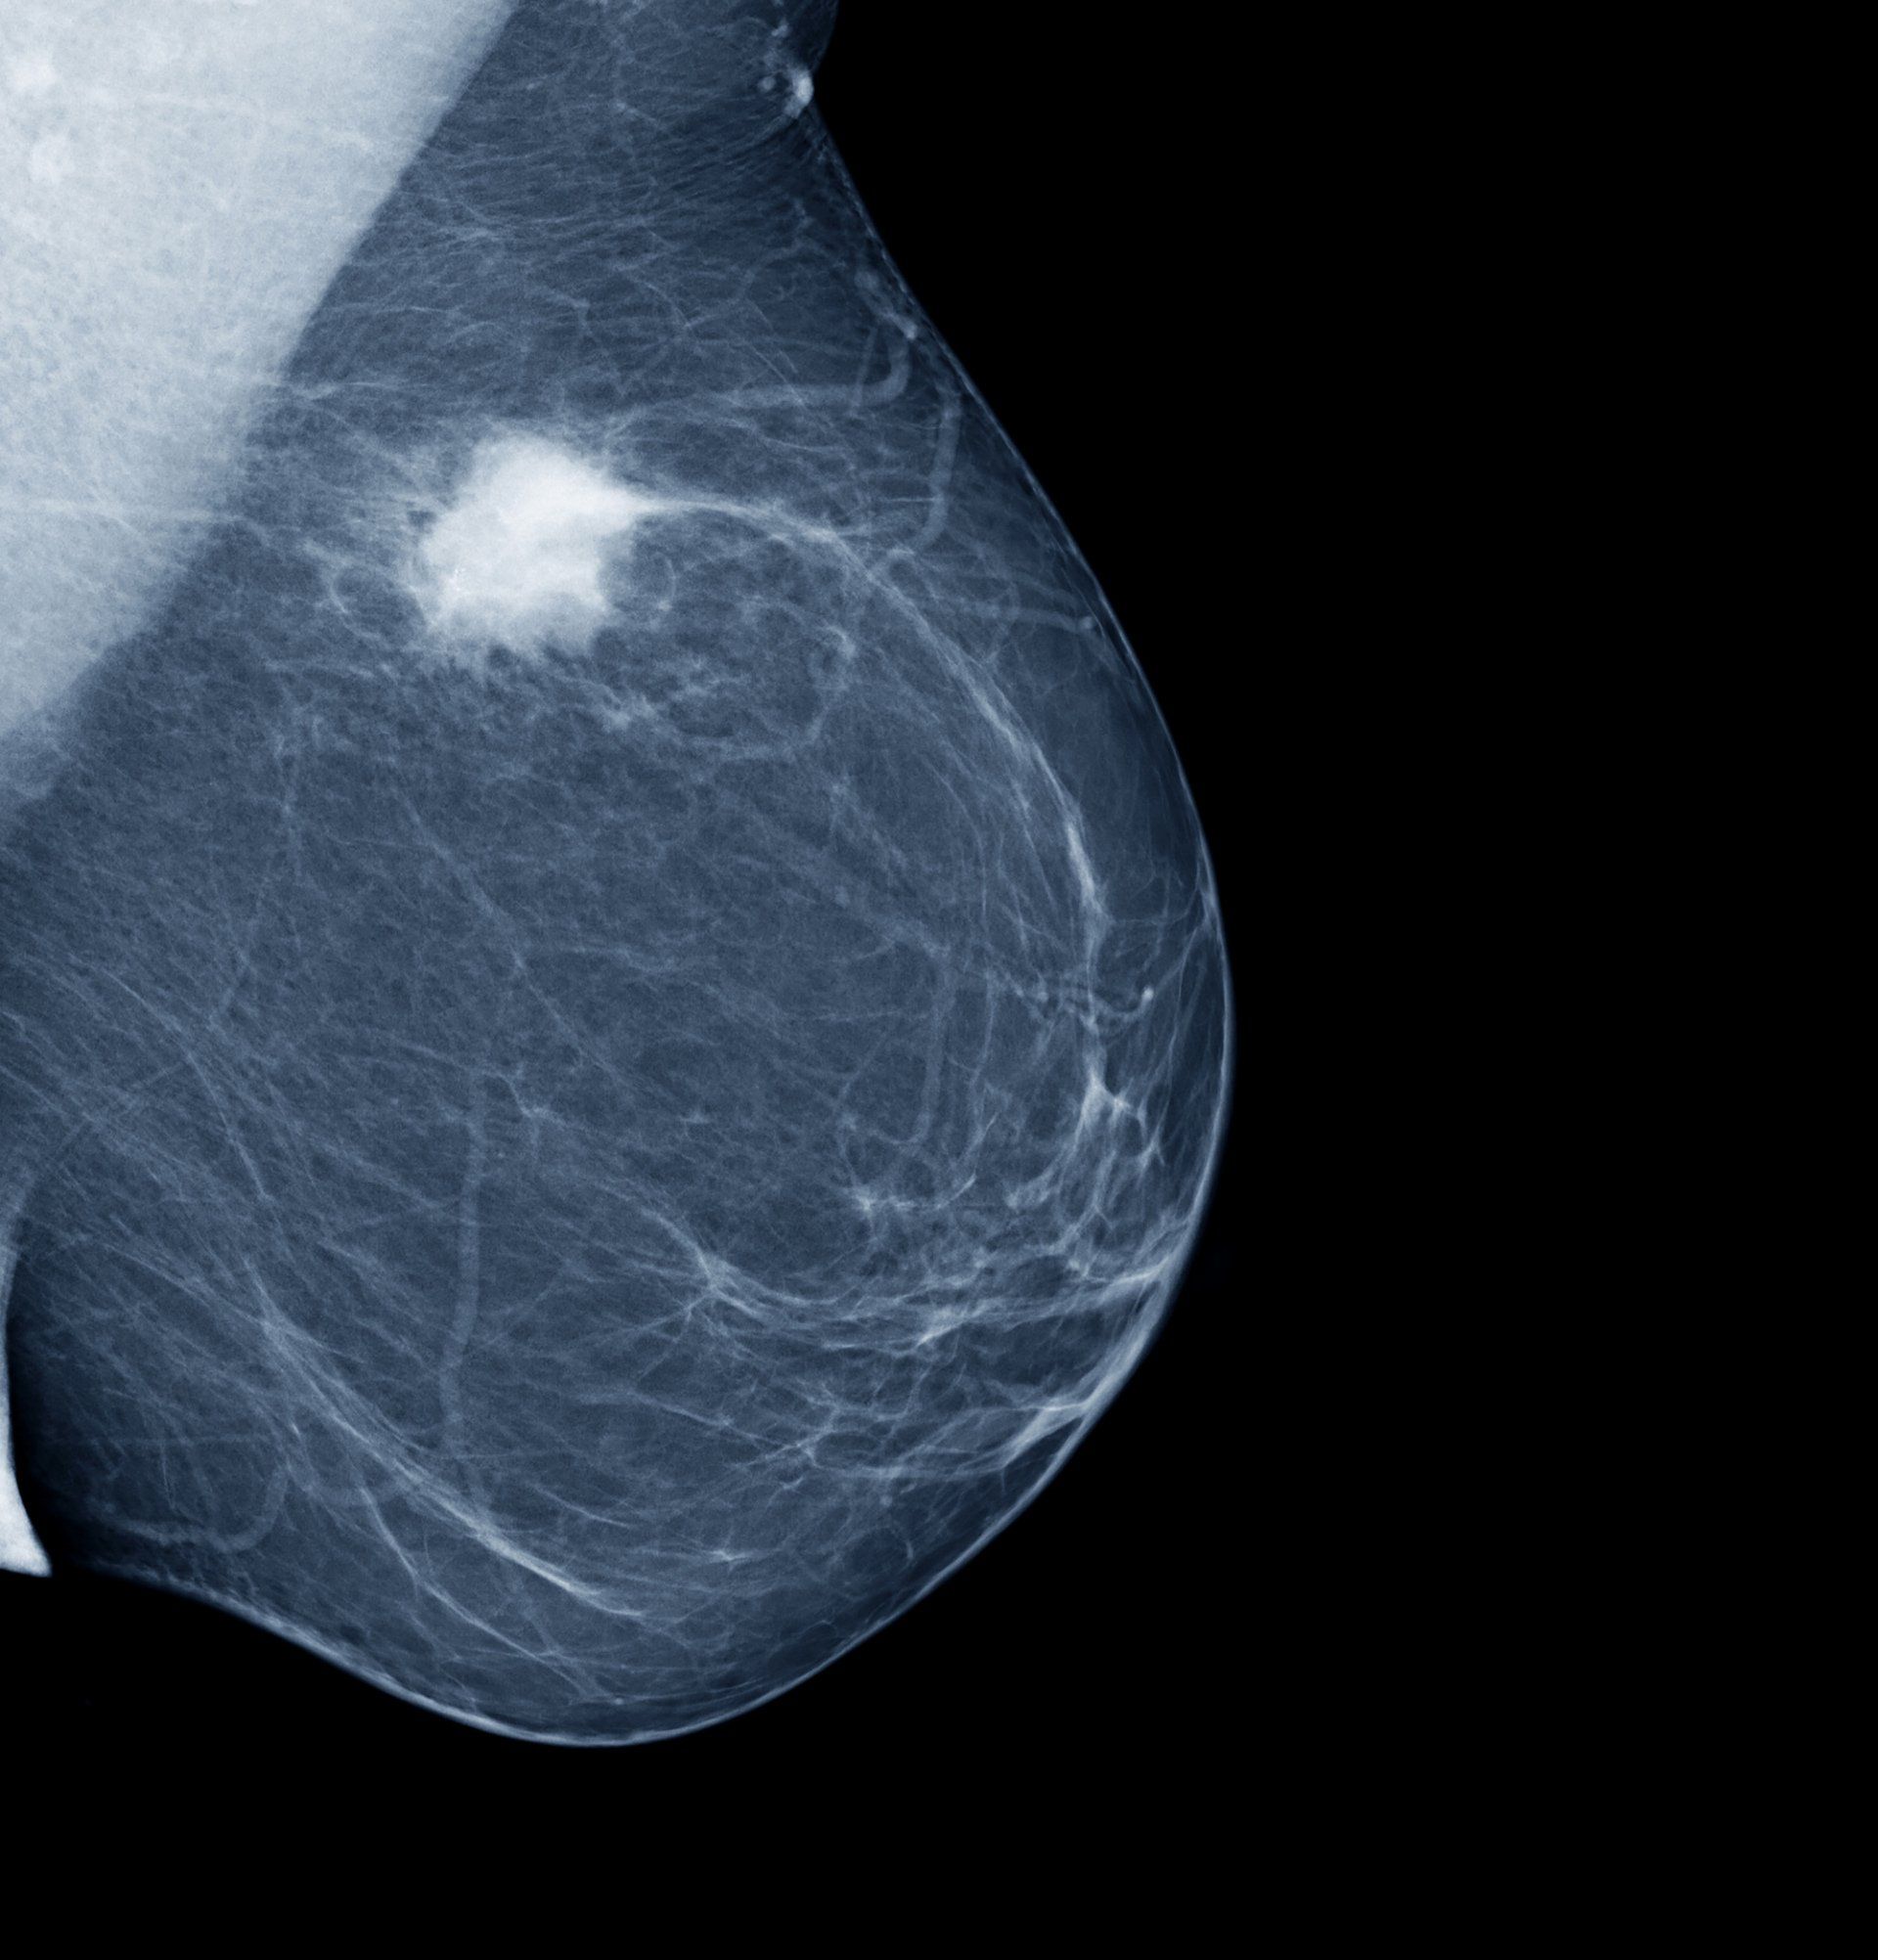

DIAGNOSTICA SENOLOGICA

Nelle strategie per il controllo del tumore alla mammella la fase diagnostica riveste da sempre un’importanza fondamentale: minori sono le sue dimensioni al momento della diagnosi maggiori sono per la donna le probabilità di guarigione definitiva.